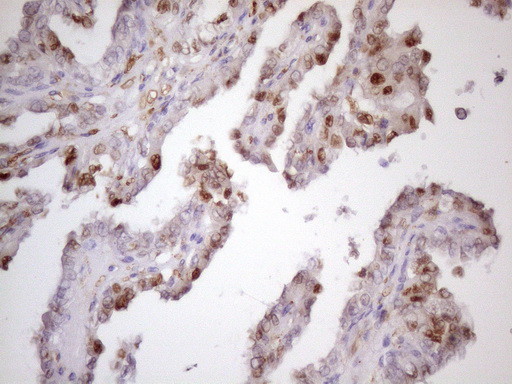

Immunohistochemical staining of paraffin-embedded Carcinoma of Human kidney tissue using anti-CDKN1A mouse monoclonal antibody. (Heat-induced epitope retrieval by 1mM EDTA in 10mM Tris, pH8.5, 120°C for 3min, M00145-4) (1:150)

Immunohistochemical staining of paraffin-embedded Carcinoma of Human thyroid tissue using anti-CDKN1A mouse monoclonal antibody. (Heat-induced epitope retrieval by 1mM EDTA in 10mM Tris, pH8.5, 120°C for 3min, M00145-4) (1:150)

Immunohistochemical staining of paraffin-embedded Carcinoma of Human kidney tissue using anti-CDKN1A mouse monoclonal antibody. (Heat-induced epitope retrieval by 1mM EDTA in 10mM Tris, pH8.5, 120°C for 3min, M00145-4) (1:150)

Immunohistochemical staining of paraffin-embedded Carcinoma of Human thyroid tissue using anti-CDKN1A mouse monoclonal antibody. (Heat-induced epitope retrieval by 1mM EDTA in 10mM Tris, pH8.5, 120°C for 3min, M00145-4) (1:150)